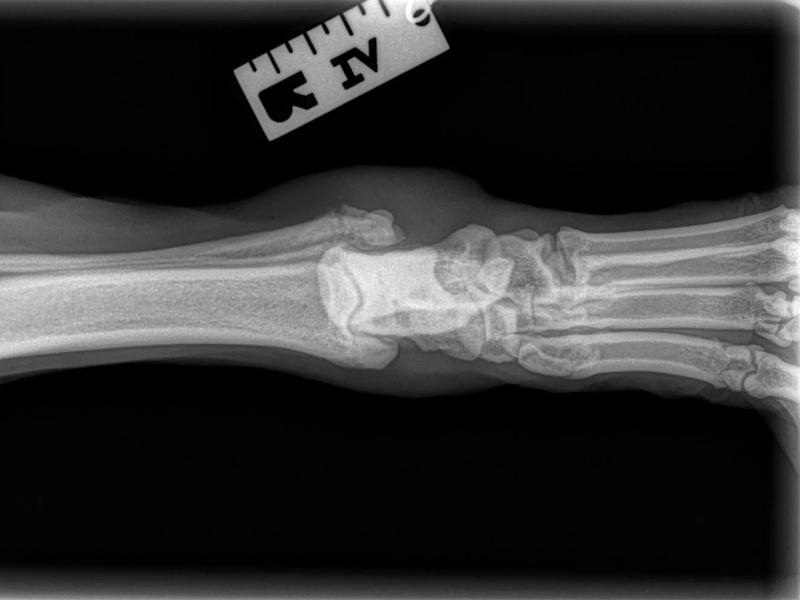

Carpal Hyperextension

Fore Limb (Humerus, Radius/Ulnar, Metacarpus)

Hind Limb (Pelvis, Femur, Patella, Tibia/Fibula, Lateral Malleolus)